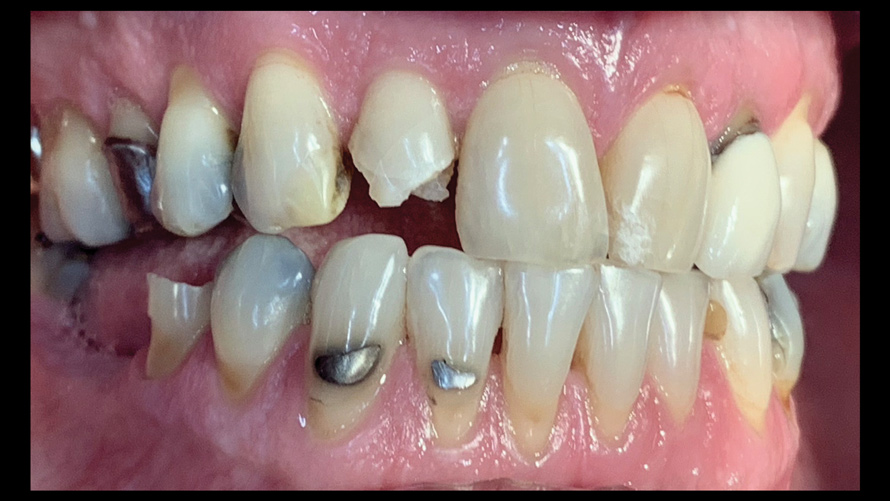

(9.) Preoperative esthetic case documentation using a smartphone and an EALS device.

Figure 9

(10.) Preoperative esthetic case documentation using a smartphone and an EALS device.

Figure 10

(11.) Preoperative esthetic case documentation using a smartphone and an EALS device.

Figure 11